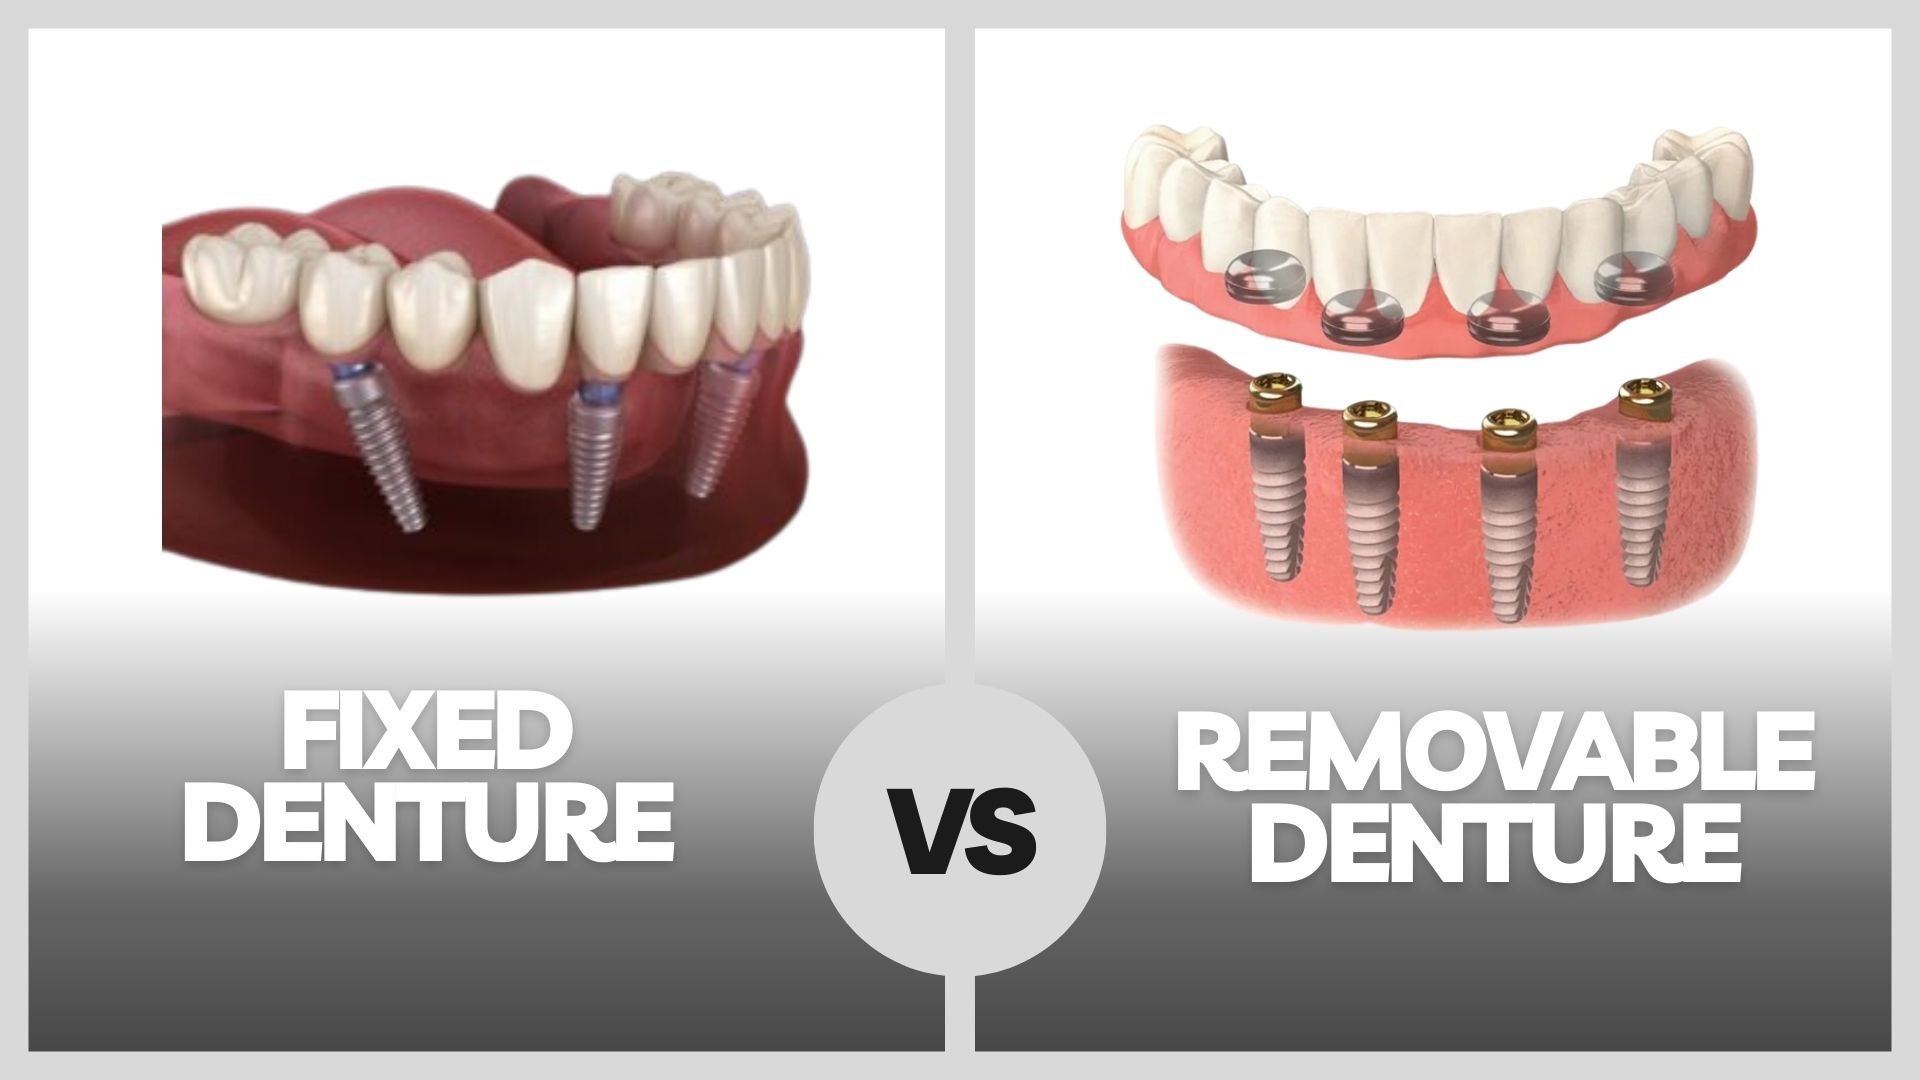

Dentures (Fixed and Removable)

Dentures are established dental service for replacing multiple missing teeth and restoring facial harmony.